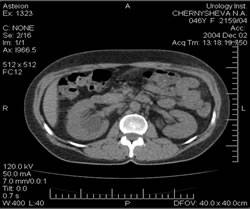

КОМПЬЮТЕРНАЯ

ТОМОГРАФИЯ: |

|